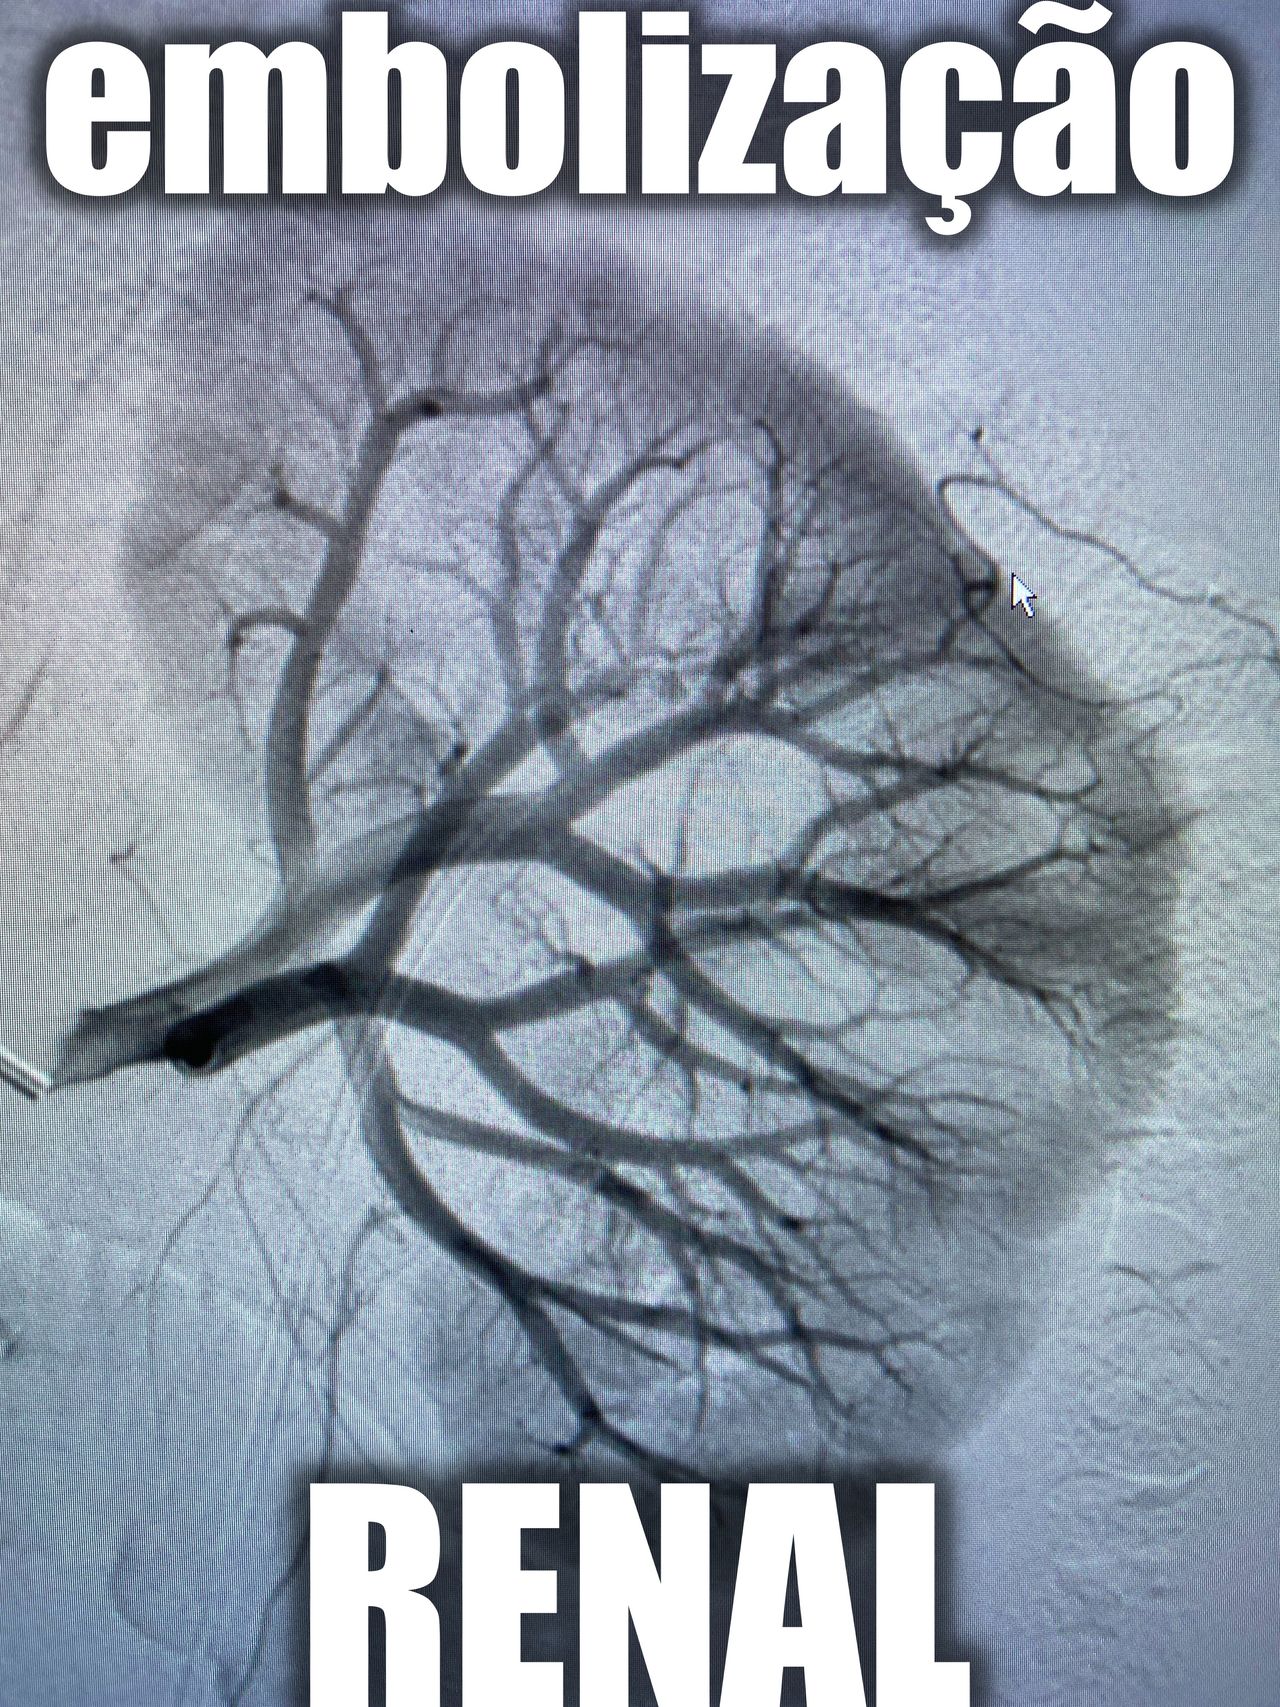

Embolizações vasculares

A partir de R$ 0 -